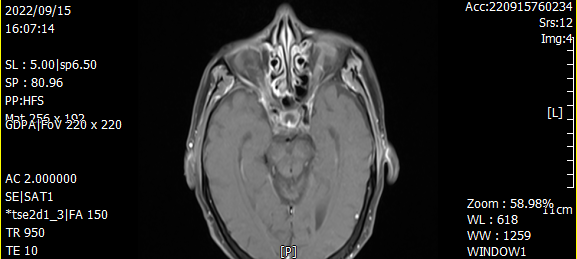

鼻咽癌治療前VS鼻咽癌治療后

60歲的林先生因反復鼻出血半年有余,且伴有雙側(cè)眼球活動障礙,診斷系鼻咽癌。之前一直在其他醫(yī)院治療,聽說我院與國科大腫瘤醫(yī)院締結(jié)院間協(xié)作,每周有國家級腫瘤專家坐診,遂轉(zhuǎn)診我院。入院后,在國科大腫瘤醫(yī)院頭頸放療專家花永虹教授的精心治療下,目前,林先生眼球已恢復正常運動功能,取得較好的治療效果,有效提高了生活質(zhì)量。